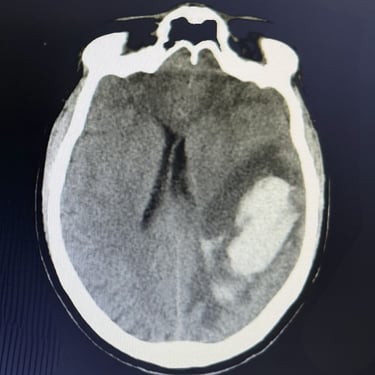

🧠Hematoma intracerebral parietal: tratamiento mediante craneotomía con evacuación de hemorragia.

El hematoma intracerebral parietal es una emergencia neurológica asociada a alta morbimortalidad. La craneotomía con evacuación del hematoma es una intervención quirúrgica indicada en casos seleccionados para reducir la presión intracraneal, limitar el daño cerebral y mejorar el pronóstico funcional en pacientes con deterioro neurológico significativo.